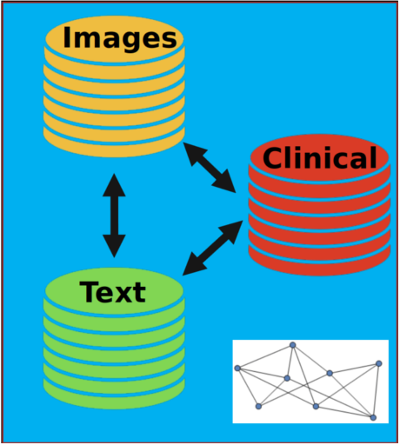

Research Area 2: Heterogeneous Data

Data from different sources can be combined to make better predictions

For example, medical imaging, physician text notes and clinical data are full of relevant information